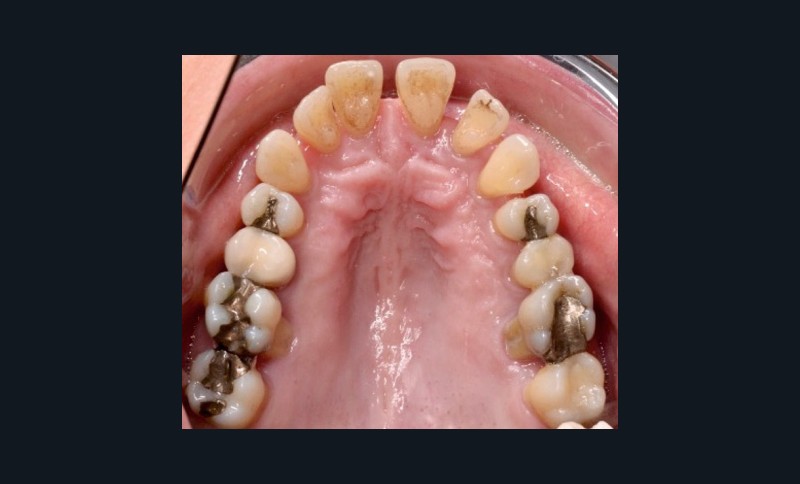

À l’examen endo-buccal (fig. 2), on note une formule dentaire complète (absence des 8) avec présence de restaurations multiples étanches, un bon contrôle de plaque et une parodontite de stade 4 grade C stabilisée [3], des récessions gingivales et des mobilités dentaires généralisées (degré 2, classification de Miller). L’arcade mandibulaire présente une courbe de spee importante avec égression du bloc incisivo-canin. Les milieux inter-incisifs sont alignés, le recouvrement est normal, le surplomb est augmenté à 3 mm et associé à des diastèmes et de la vestibulo-version des incisives maxillaires. Les relations antéro-postérieures canine et molaire sont en Classe I d’Angle.